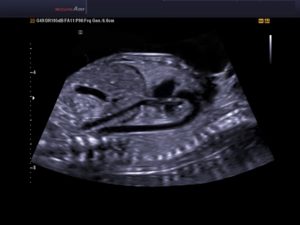

Визуальное изучение структур сердечнососудистой системы эмбриона, используя ультразвук – эхокардиография. УЗИ сердца плода можно делать как через переднюю брюшную стенку (трансабдоминально), так и через половые пути женщины (трансвагинально).

На малом сроке предпочтение отдают трансвагинальному способу, так как сердцебиение плода различимо только после четвертой недели. На шестой неделе сокращение сердца плода удаётся различить и при трансабдоминальном способе. При первом скрининге могут использовать два способа с целью лучшей визуализации сердца.

При использовании трансабдоминального способа желательно не мочится перед исследованием, чтобы лучше визуализировалась полость матки, которую приподнимает наполненный мочевой пузырь. При трансвагинальном способе, перед процедурой мочевой пузырь нужно опорожнить.

УЗИ принято делать в положении лежа на спине. На живот наносят гель и водят датчиком по поверхности живота, при этом на мониторе будут виден эмбрион и интересующие доктора структуры.

При втором способе во влагалище вводят соответствующий датчик, на который одет специальный презерватив. Датчик погружают на необходимую глубину и производят необходимые расчеты и измерения.